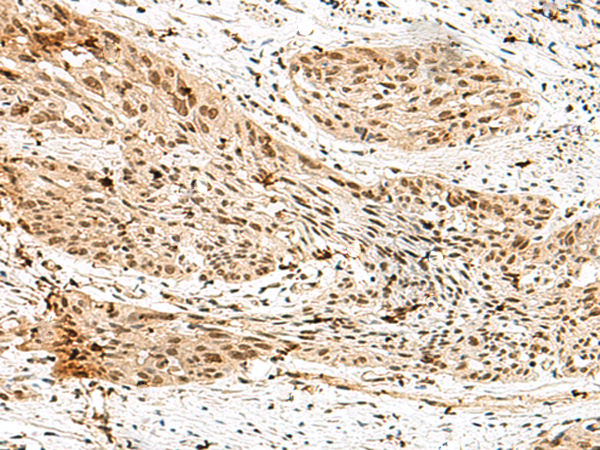

IHC positive control:

Human esophagus cancer and Human tonsil

IHC Recommend dilution:

30-150